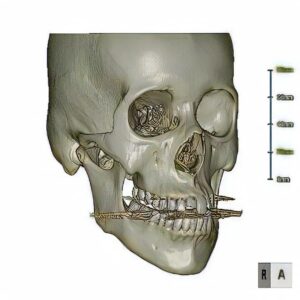

当院では、ステントを作成後、あご骨まわりのCT撮影を行い、事前に骨の状態や骨の中の血管・神経などの位置、インプラントを入れる位置を確認しています。

ステントとは、マウスピースのような形状をしており、インプラントを植え込む際の補助具です。

人工の歯を入れるわけですから、かみ合わせはもちろんのこと、周囲の歯に合わせて大きさや傾きなど、歯の設計をする必要があります。その補助となるのがステントです。上下の歯形をとり、これに合わせてステントと呼ばれるマウスピースを作成します。

このステントを装着した状態で、CT撮影を行い、どこにインプラントを入れ、どのように歯を並べられるかを調べます。同時に、撮影データを使いパソコン上で手術シミュレーションを行うことにより、手術前に上記の偶発症・合併症などの手術リスクを評価していきます。

また、シミュレーションを行った角度を寸分違わず行うために、ガイドと呼ばれるマウスピースを作成します。

ステントは「歯を設計するためのもの」で、ガイドは「手術をするためのもの」と考えて頂ければ良いでしょう。